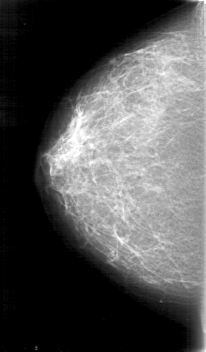

D_4075_1.LEFT_MLO

D_4075_1.LEFT_CC

LEFT_MLO LINES 5251 PIXELS_PER_LINE 3136 BITS_PER_PIXEL 12 RESOLUTION 43.5 OVERLAY

FILE: D_4075_1.LEFT_CC.OVERLAY

TOTAL_ABNORMALITIES 1

ABNORMALITY 1

LESION_TYPE MASS SHAPE LOBULATED MARGINS CIRCUMSCRIBED

ASSESSMENT 0

SUBTLETY 5

PATHOLOGY BENIGN

TOTAL_OUTLINES 1

BOUNDARY